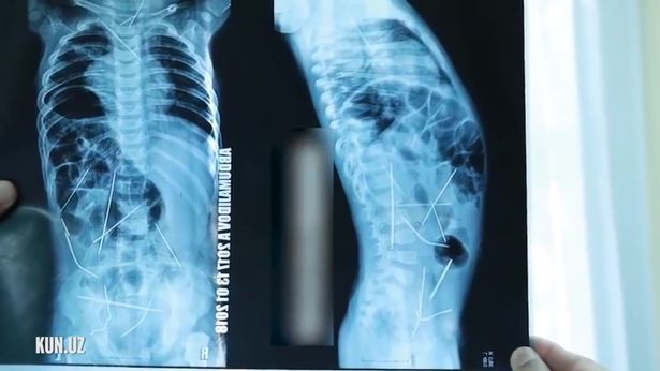

Các bác sĩ phát hiện 16 cây kim khâu nằm rải rác trong cơ thể em bé sau khi chụp X-quang.

Bà mẹ đến từ Uzbekistan phát hiện con có biểu hiện sốt cao và đi tiểu khó nên đưa con nhập viện khám. Sau khi chụp X-quang, bà sốc toàn tập khi nhận được kết quả có tới 16 cây kim khâu trong cơ thể con, nằm rải rác trong tim, cổ, cột sống, đại tràng và bàng quang.

16 cây kim khâu nằm ở các vị trí khác nhau trong cơ thể cậu bé: tim, cổ họng, cột sống, đại trang và bàng quang.